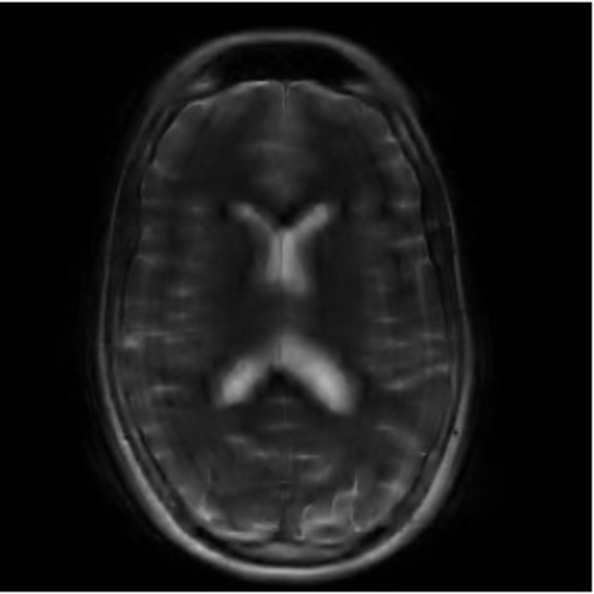

Refer to caption

Figure 3: Pixel-wise standard deviations of reconstructions across 10 random k-space sampling masks (R=7R=7) of the same slice. Top to Bottom: models trained on 100, 500, and 1000 slices. PaDIS-MRI consistently exhibits lower pixel-wise variance (fewer bright regions) than FastMRI-EDM across training sizes and contrast types, indicating more stable reconstruction.

We assess reconstruction consistency by evaluating variability across 10 random k-space undersampling patterns (generated with different random seeds) for the same slice. Since the ground truth image is the same across undersampling masks, lower pixel-wise standard deviation indicates more stable reconstruction. We emphasize this is a consistency metric rather than calibrated posterior uncertainty. Such reliability is of particular interest to clinical settings where higher model consistency paired with superior accuracy can enhance medical decision-making.

Figure 3 visualizes these standard deviation maps, with brighter regions indicating higher variability between reconstructions. Across the 100-slice, 500-slice, and 1000-slice training regimes, PaDIS-MRI exhibits noticeably lower pixel-wise standard deviations compared to FastMRI-EDM, with the largest differences occurring at the smaller training dataset sizes. This suggests that decomposing the reconstruction problem into localized patches enables more stable learning of anatomical features, resulting in more reliable and consistent predictions from limited training data.